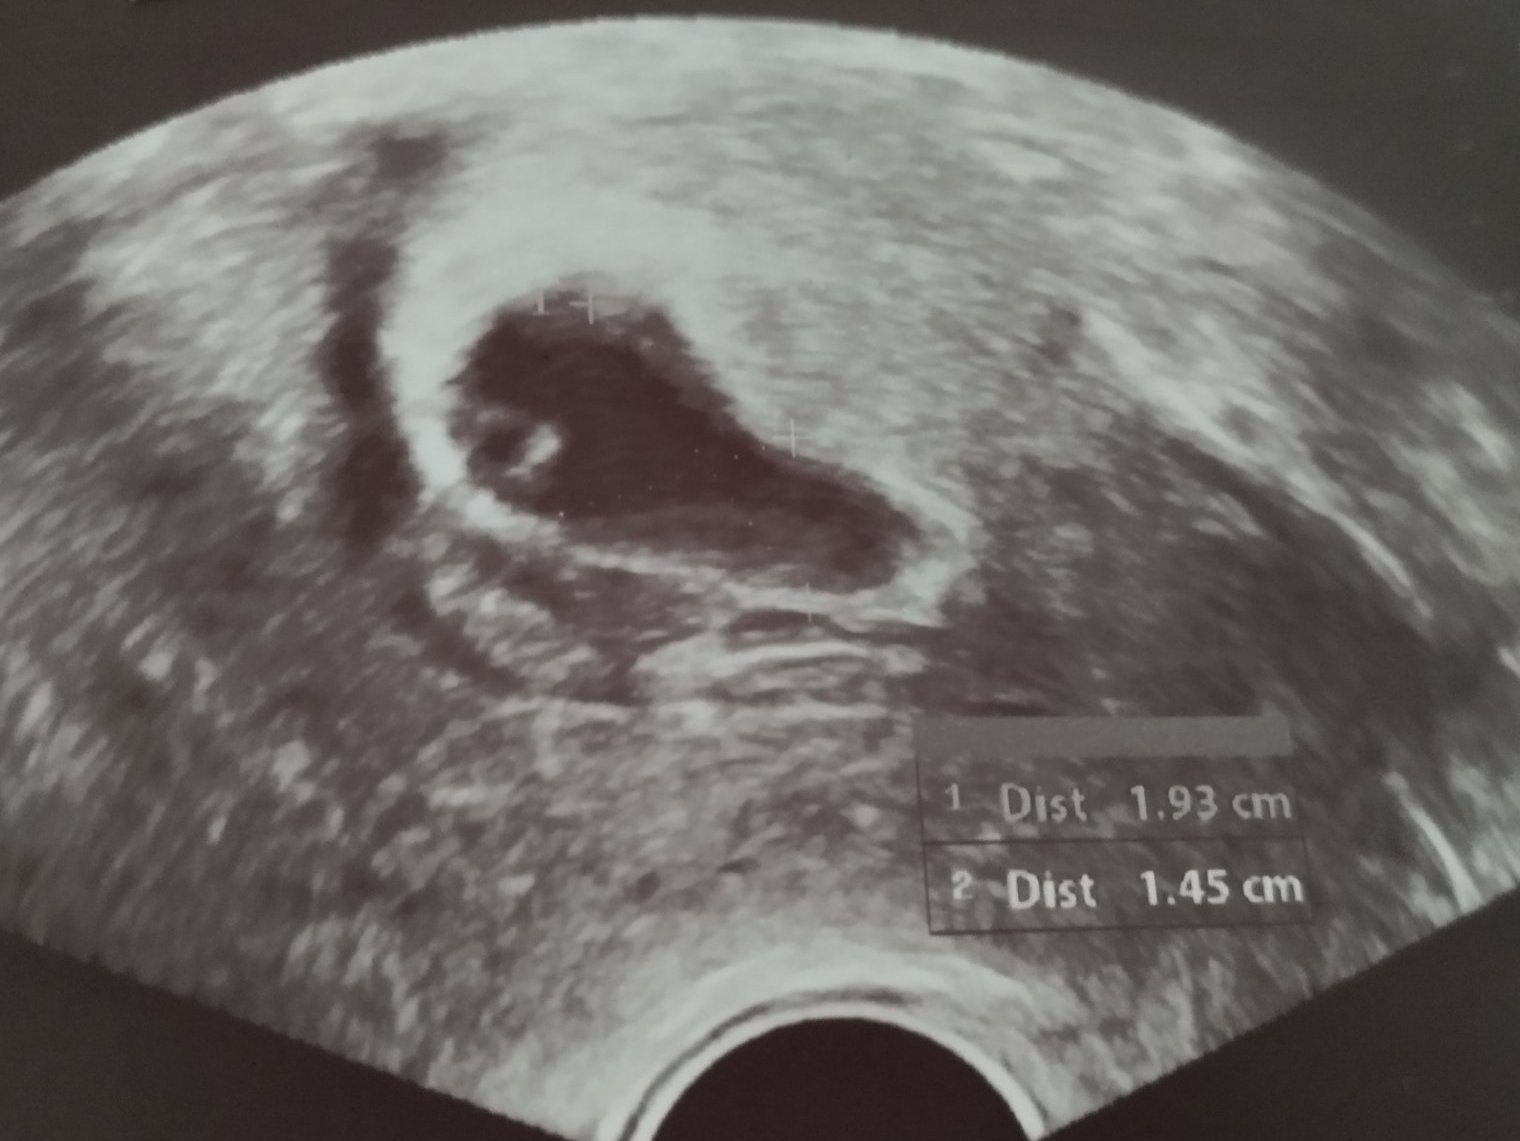

В 5+3 г.с. прокървява за кратко с червена кръв. Докато иде в болницата, кръвта е спряла. Вижда се перфектно позициониран плоден сак с размери 8:6 ММ. В матката има кръв, но лекарката я успокоява, че няма хематоми и вероятно е хормонално излющване и може да има такова до 5 месец, вкл. може да е обилно.

Днес след ставане е почнало кървене със съсиреци. Отишла е на лекар. Плодният сак е 18:16 ММ. Има ембрионална структура, жълтъчно мехурче и зачатъци на сърдечна дейност, но още няма сърдечен ритъм и сакчето изглежда леко издължено в единия край, но не е сигурно дали не е сянка от хематом (има леко недозалепяне в единия край). В матката има кръв и съсиреци, които ще падат тепърва. Изписани са ѝ лекарства и лежане. След седмица я викат и при наличие на сърдечна дейност ще я приемат в болница, при липса - вероятно ще я ююретират.

Ето и снимка от днес (не мога да я сложа цялата, че има и лични данни). Как ви се струва? Някоя минала ли е през обилни кръвотечения със съсиреци и бебето да се е запазило и родило здраво?